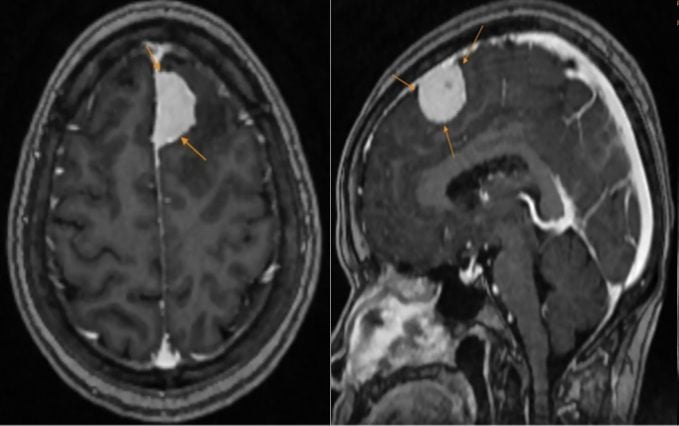

| Rentgenový snímek pacienta. |

Výsledky magnetické rezonance paní H. překvapily, když na levé straně čela objevila velký nádor o rozměrech přibližně 27x15 mm, s podezřením na meningiom. Díky včasnému odhalení lékař doporučil bezpečný a účinný intervenční plán, který omezil riziko komplikací.

Meningeomy jsou nádory, které se vyvíjejí z arachnoidální vrstvy mozkových plen a tvoří přibližně 15 % mozkových nádorů. Toto onemocnění se může objevit v jakémkoli věku, ale je častější u dospělých a žen než u mužů. Většina meningeomů roste pomalu a je benigní, ale některé mohou být maligní.

MSc. Le Quynh Son z oddělení diagnostické zobrazovací metody všeobecné kliniky MEDLATEC Cau Giay uvedl, že magnetická rezonance (MRI) a počítačová tomografie (CT) jsou předními zobrazovacími diagnostickými nástroji při hodnocení lézí mozkových nádorů. Tyto dvě techniky nejen přesně určují umístění a velikost nádoru, ale také poskytují vícerozměrný pohled na vztah mezi lézí a okolními mozkovými strukturami.